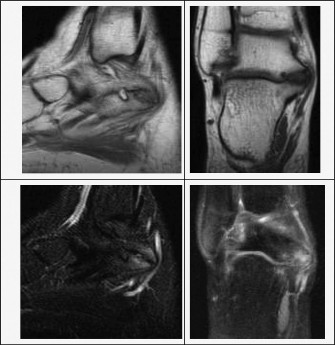

Computed Tomography (CT) is the gold standard for mapping the exact three-dimensional anatomy of the coalition. For TC coalitions, coronal CT slices perpendicular to the posterior facet are critical for calculating the percentage of joint surface involved. A coalition involving more than 50% of the posterior facet surface area is generally considered a contraindication to simple resection, as the remaining joint will likely be unstable and degenerate rapidly; these cases are better served by subtalar arthrodesis. Magnetic Resonance Imaging (MRI) is reserved for cases where a fibrous or cartilaginous coalition is suspected but not clearly visible on CT, or to evaluate the integrity of the surrounding cartilage and tendons.